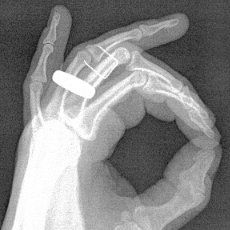

That’s what I’m doing today thanks to a relatively freak accident with a staple gun yesterday. I won’t bore you with the details (that would confirm what a bonehead I can be sometimes). Just suffice it to say that, it could have been a lot worse.